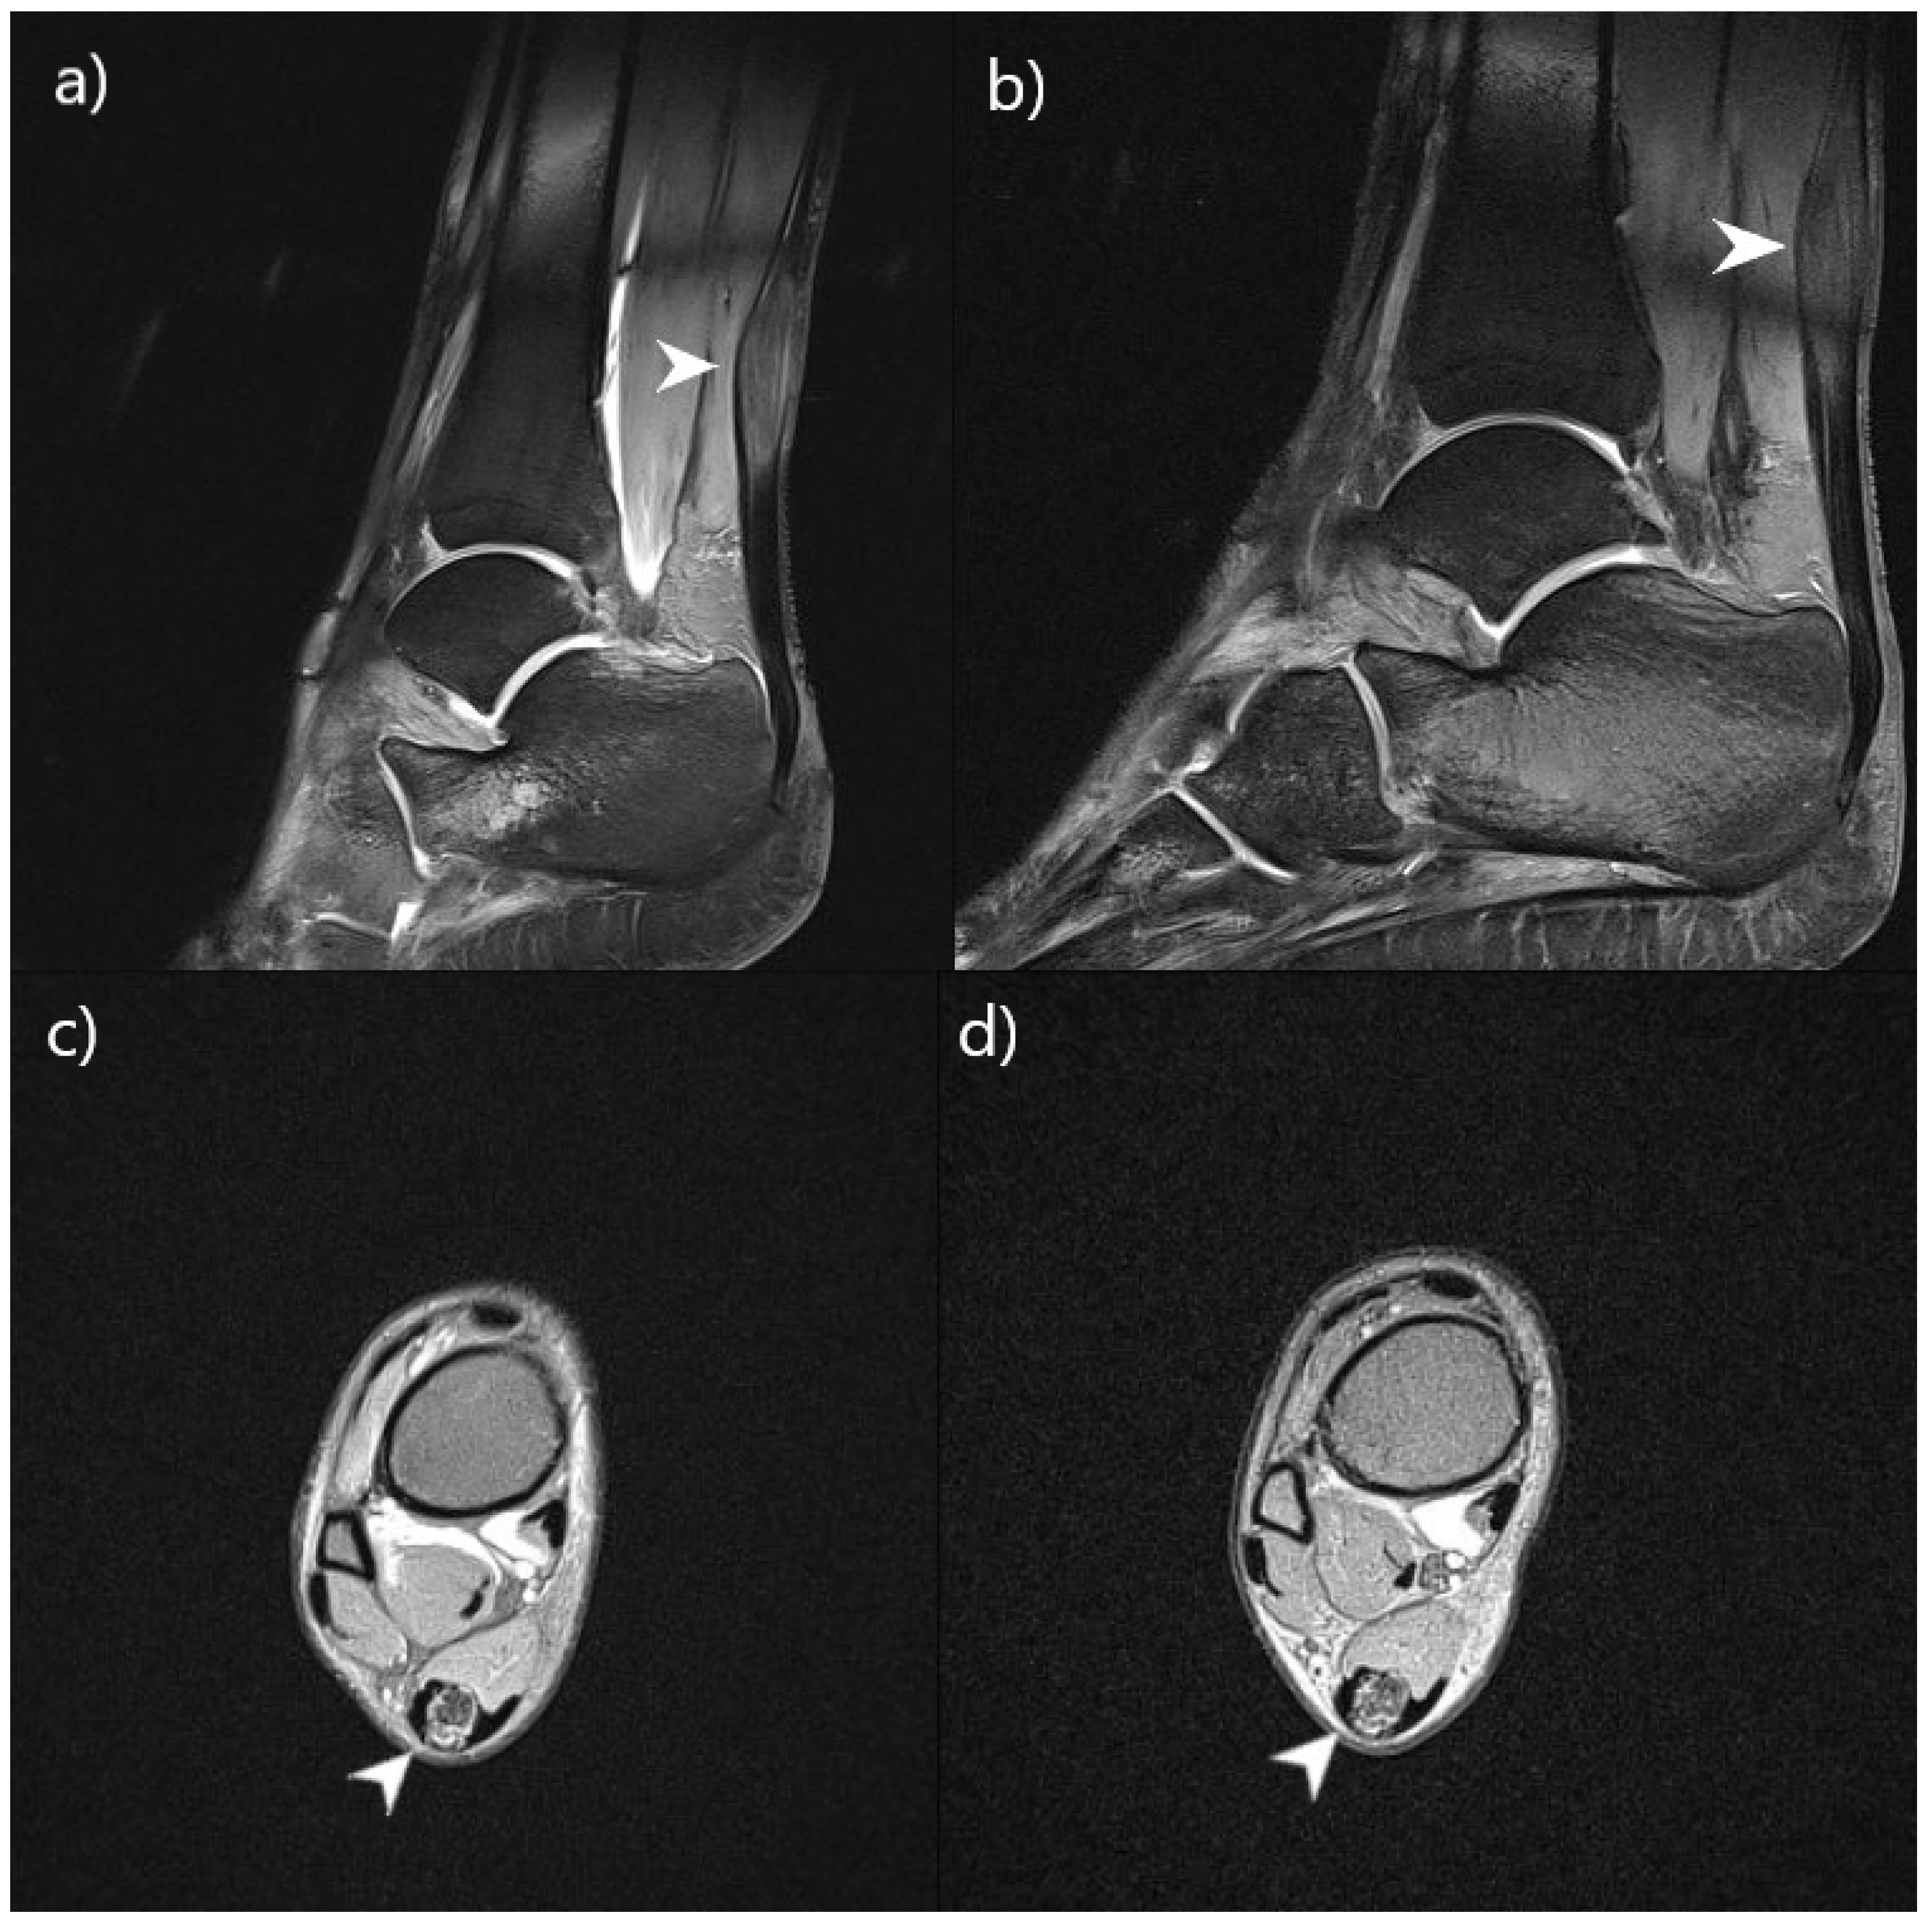

| Achilles tendon abnormalities on MRI | + | + | / | / | Without progression | Without progression |